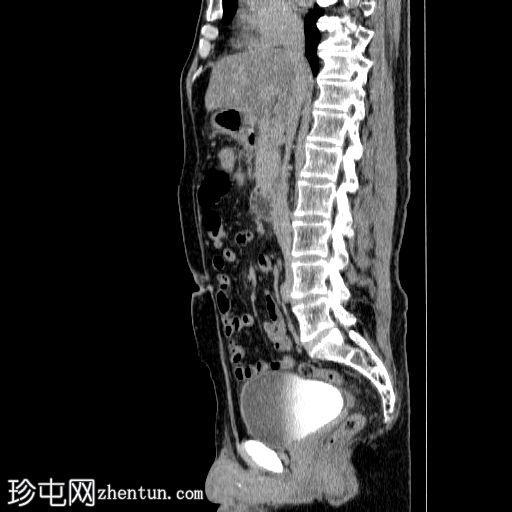

3.jpg

矢状面

胰体尾弥漫性增大,特征为胰腺实质低强化,无明显坏死区域。

该病灶与以下表现相关:

胰周筋膜平面边界不清的污迹,无明显壁形成、气室、固体碎片或血液产物。

病变范围如下:

病变横向延伸至左前肾旁间隙,伴有Gerota筋膜增厚。

病变向下延伸至盆腔。

无肠系膜或脾脏血管阻塞的证据。

未见导管扩张或钙化。